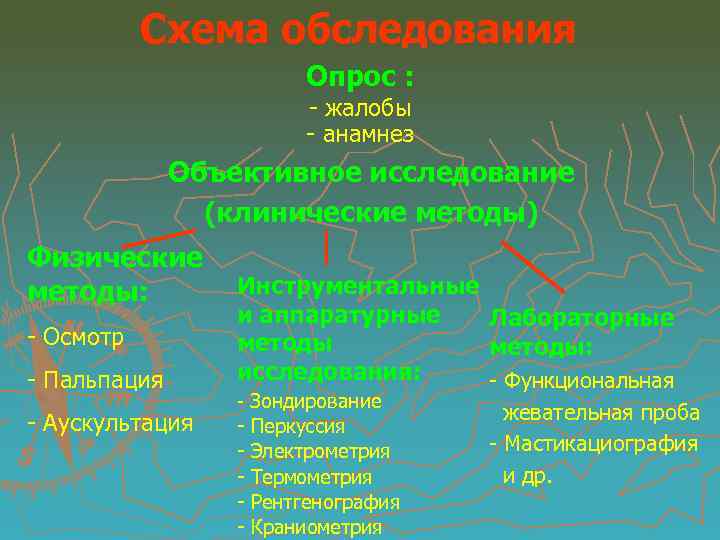

Схема обследования Опрос : - жалобы - анамнез Объективное исследование (клинические методы) Физические методы: - Осмотр - Пальпация - Аускультация Инструментальные и аппаратурные Лабораторные методы: исследования: - Функциональная - Зондирование Перкуссия Электрометрия Термометрия Рентгенография Краниометрия жевательная проба - Мастикациография и др.